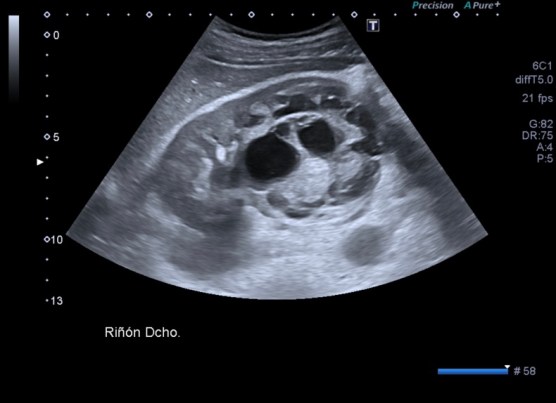

Lesión heterogénea, en el meso-riñón derecho, redonda, típica de quiste hidatídico.

Después de ver esta maravilla de imágenes, habiendo repasado el post 262 donde te explico las claves del quiste hidatídico, no tengo nada más que decir. Las imágenes hablan por si mismas. Perfectas, con una calidad increíble, el equipo increíble, bien ajustado, los parámetros adecuados, es un estudio perfecto, Sandra…yo lo sabía y te lo decía y estoy orgulloso, muy orgulloso de hacer esto que estoy haciendo ahora, en el día 2.

Un quiste hidatídico renal, maravilloso.